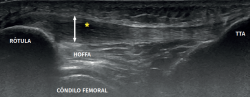

The most common MRI finding is increased signal intensity in the lower pole of the patella, with local widening of the affected zone of the tendon (Figure 7)(14,25). The most evident advantage of MRI with respect to ultrasound is its capacity to visualise associated lesions in the joint and cartilage, as well as the presence of bone edema and involvement of Hoffa's fat pad (Figure 7). As clear disadvantages, mention must be made of the high cost of the technique and the impossibility of performing exploration in motion or at different angles of flexion of the knee.

Figure 7. Magnetic resonance imaging view showing alteration of the proximal patellar tendon with thickening and edema (white arrow), in a segment measuring 1.5 cm in length. Marked edema of adjacent Hoffa's fat pad (asterisk).